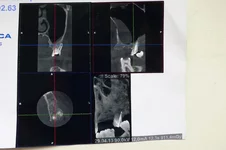

Вот снимки.Проблема с 7 слева вверху.Обязательно в неотложку или нет?Какая-то тень в поликлинике не понравилась хирургу.

В неотложку вам не надо. С зубом все в порядке. А увеличение толщины слизистой гайморовой пазухи вызвано либо не корректной проекцией КТ либо ЛОР проблемами.Вот снимки.Проблема с 7 слева вверху.Обязательно в неотложку или нет?Какая-то тень в поликлинике не понравилась хирургу.

Я написала про не корректную проекцию. КТ надо смотреть как трехмерное изображение. Поэтому смотрят КТ в разных проекциях.

Р.S. Еще раз. С зубом проблем нет.

Спасибо.Диагноз( что смогла прочитать)- хронич.периодонтит,гайморит.Так гайморит уже лет10 беспокоит-зачем в неотложку?Мне один стоматолог посоветовал полоскание с солью и "все пройдет,зуб сохраним". Опухоль чуть спала,но зуб же все равно надо удалять?

Смотрите. Вот стрелкой я пометила причину гайморита.

А вот причина дИкого мЯса. Не запломбированый канал

Если запломбировать канал, то зуб удалять не надо

Но точнее можно сказать если посмотреть диск.